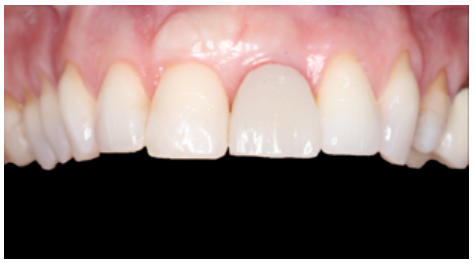

At the intraoral level, a mid-smile line and fine gingival biotype was observed, accompanied by gingival recessions at the level of the upper right central incisor (URCI), as well as in the first, third and fifth sextant teeth. There was slight crowding in the lower anterior region and evidence of multiple dental treatments, such as root canals and osseointegrated implants (OII).

Erythematous mucosa was observed In the ULCI region, accompanied by inflammation of the apical region of the tooth at the level of the attached gingiva, suspected to be due to a periapical abscess following infection of the tooth (Figure 1). The ULCI had great mobility due to a radicular fracture not observed on clinical examination.

Given the good evolution at 6 months, the position of the OII and the emergence profile were recorded via an individualised transfer to replicate the gingival architecture faithfully and in detail (Figures 26 and 27). The final fixed prosthesis screwed to the OII was inserted 7 months after the treatment had started (Figures 28 and 29).